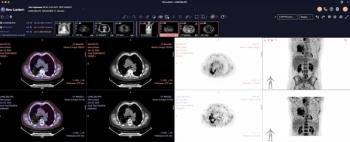

Combining sub-second load times and AI-automated features, the PET/CT Viewer Mode and Mammography Viewer Mode may help address bottlenecks in nuclear medicine imaging and mammography workflows.